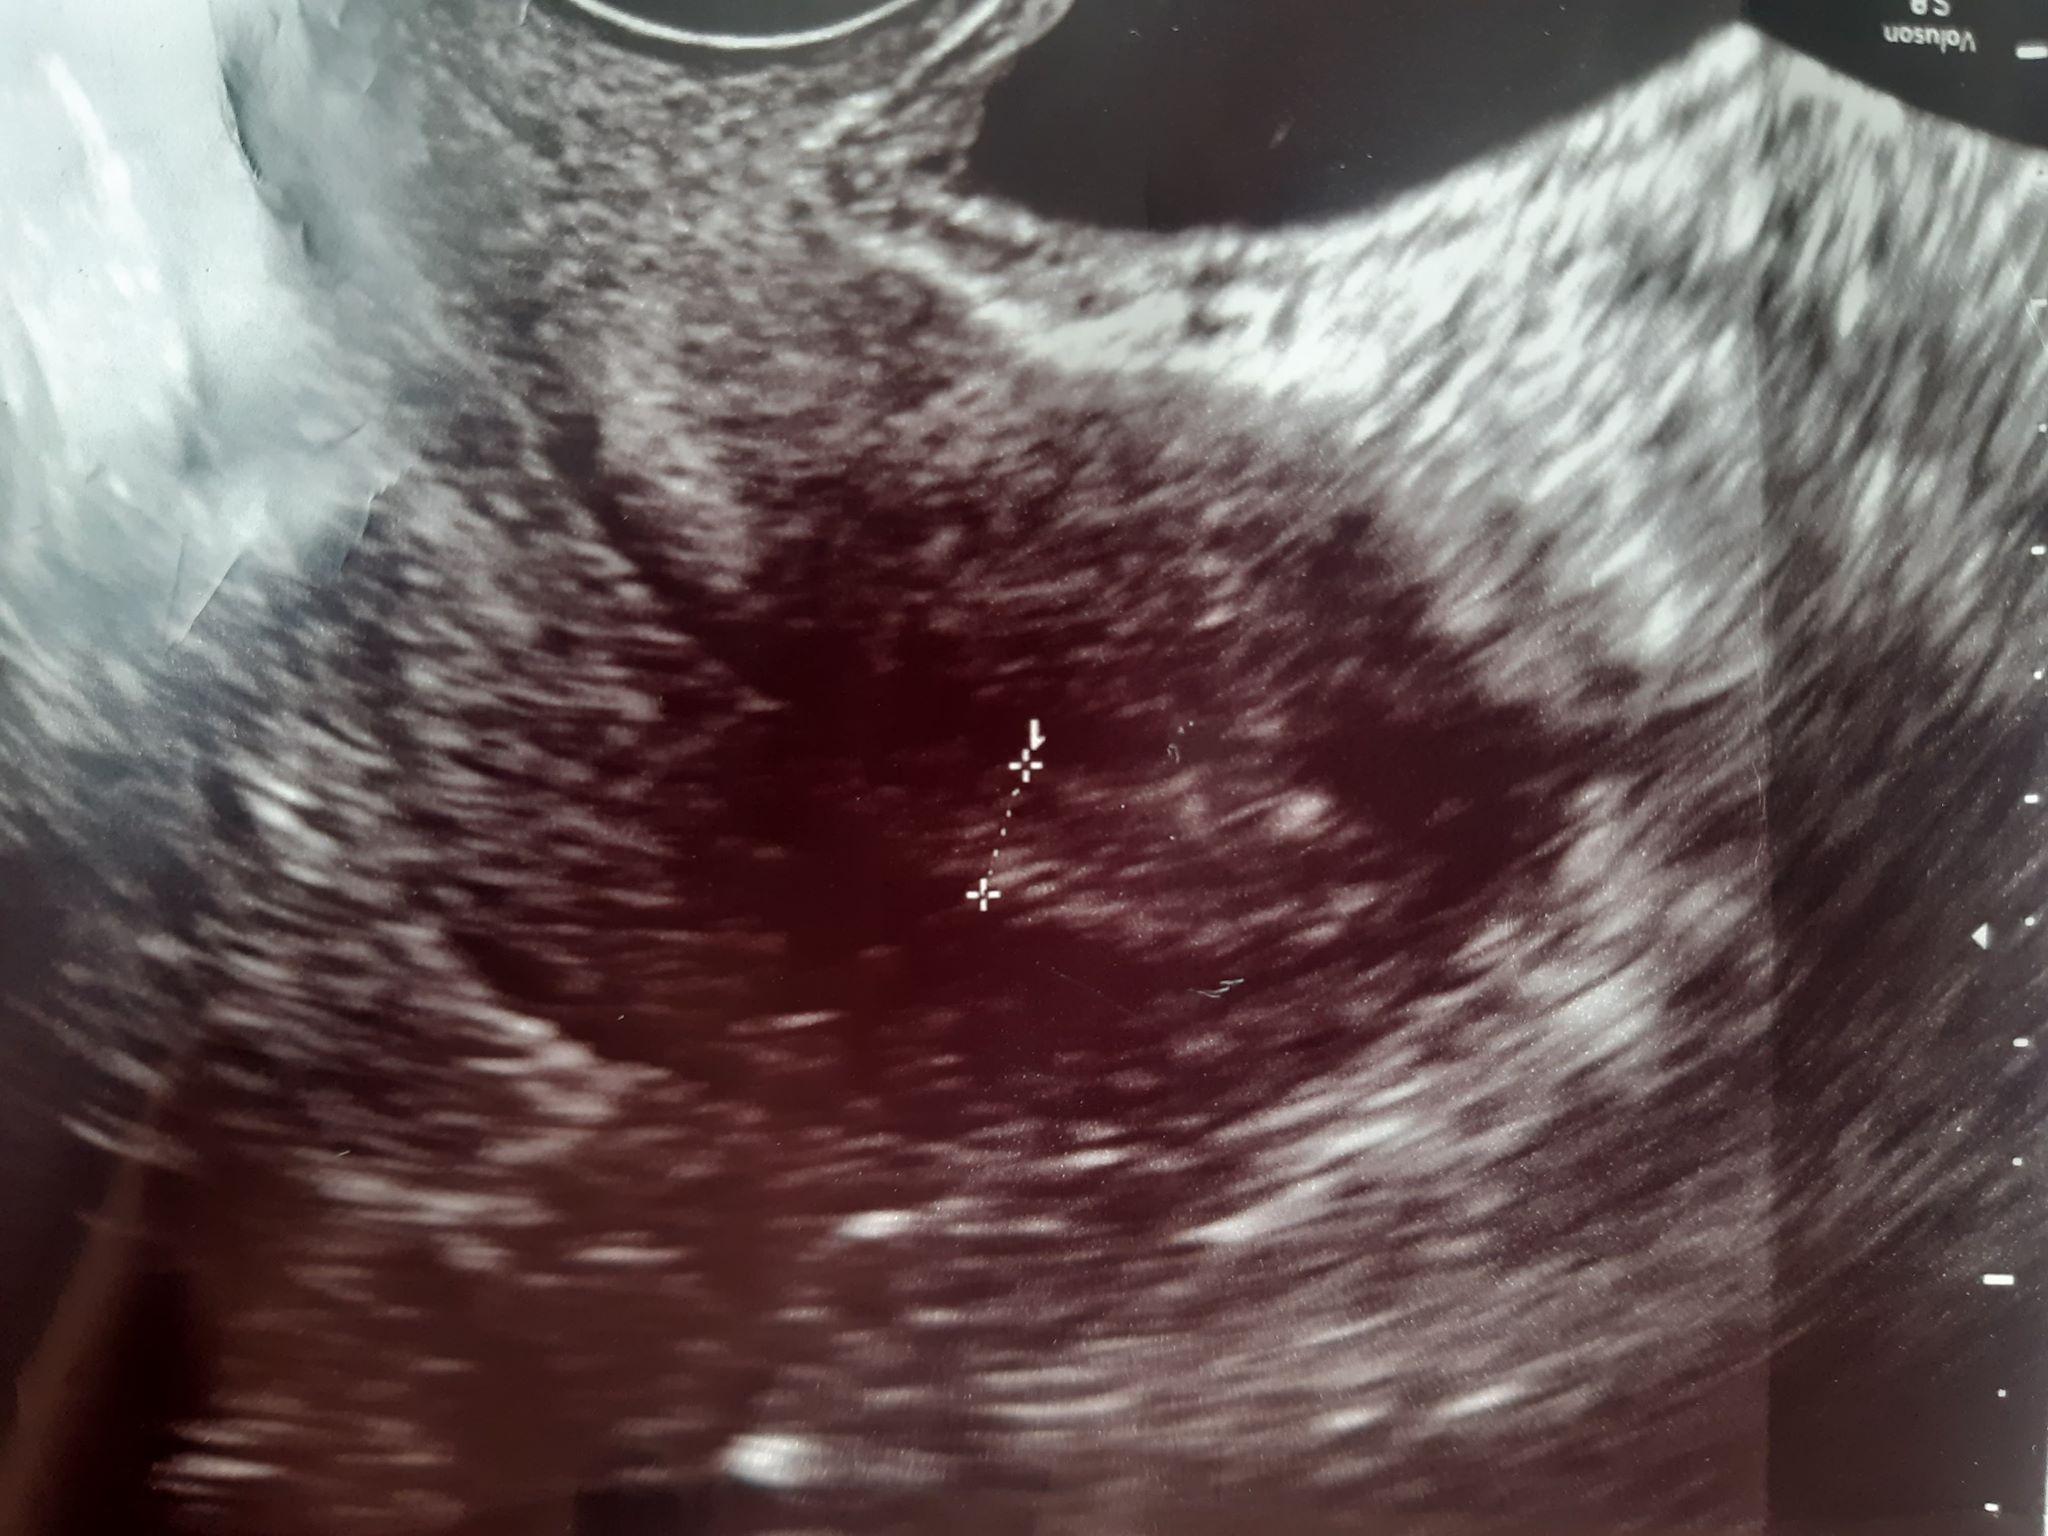

AnonymBruker Skrevet 13. august 2020 #1 Skrevet 13. august 2020 Jeg klarer ikke tyde mitt eget ultralydbilde. Er det noen erfarne som har tatt ultralyd før? Dette er første gangen min som gravid med ultralyd. Jeg var 5 uker på veg her. Det stod, 1 cm nedenfor. Den streken, hva er det den måler? For meg, ser jeg kun noe som kunne vært en fot. Men er ikke sikker, fikk ikke så mye informasjon fra gynekologen heller, annet at jeg kun kunne være 5 uker på veg utfra bildet. Anonymkode: 7efa4...49d

AnonymBruker Skrevet 13. august 2020 #2 Skrevet 13. august 2020 Hvis du er 5 uker gravid er embryoet maks 6 mm, så det er neppe det som er målt, og det er ikke noen føtter så tidlig. Det kan muligens være fostersekk eller noe. Anonymkode: 74b50...459 7

AnonymBruker Skrevet 13. august 2020 #3 Skrevet 13. august 2020 Om du er 5 cm på vei, er det nok selve embryoet som er 1 cm, og som er det som er markert. Embryoet har ikke føtter ennå... Anbefaler at du laster ned en app, f.eks. Ovia, så får du ukentlige/daglige beskrivelser av utviklingen til fosteret. Anonymkode: 315f2...17c 2

AnonymBruker Skrevet 13. august 2020 #4 Skrevet 13. august 2020 Det er vel måling av emryro. Str kan fortelle hvor langt du er på vei Anonymkode: 60fb9...bfd

AnonymBruker Skrevet 13. august 2020 #5 Skrevet 13. august 2020 Det stod, ! D 0,59cm. Hva betyr dette? Har lest meg opp, og det skal være "størrelse" på fosteret. Men, det er da større enn 5 mm? Jeg er ikke flink i matte, men får søke meg opp. Forstår ikke forklaringen til gynekolog og det som står på ultralyd bilde.. Anonymkode: 7efa4...49d

AnonymBruker Skrevet 13. august 2020 #6 Skrevet 13. august 2020 Fant ut at 1 cm = 10 mm. Hun sa 5 uker, men bommet hun da? Anonymkode: 7efa4...49d

AnonymBruker Skrevet 13. august 2020 #12 Skrevet 13. august 2020 I uke 5 er man så tidlig på vei at man ikke nødvendigvis ser noe fosteranlegg. Tipper det er str på fostersekk som er målt. Hvis du har fått pos g-test er du gravid. Hvordan svangerskapet utvikler seg må du bare vente å se. Anonymkode: 6f4a7...cb3

AnonymBruker Skrevet 13. august 2020 #16 Skrevet 13. august 2020 Men da vet jeg det, at dette kan være fostersekken. Fikk jeg ikke høre hos gynekolog, så da får jeg tenke det. Så får jeg se om jeg får positiv graviditetstest en dag, hører noen svømmelyder fra magen men kan også være rumling/ luft. Ikke godt å vite. Anonymkode: 7efa4...49d